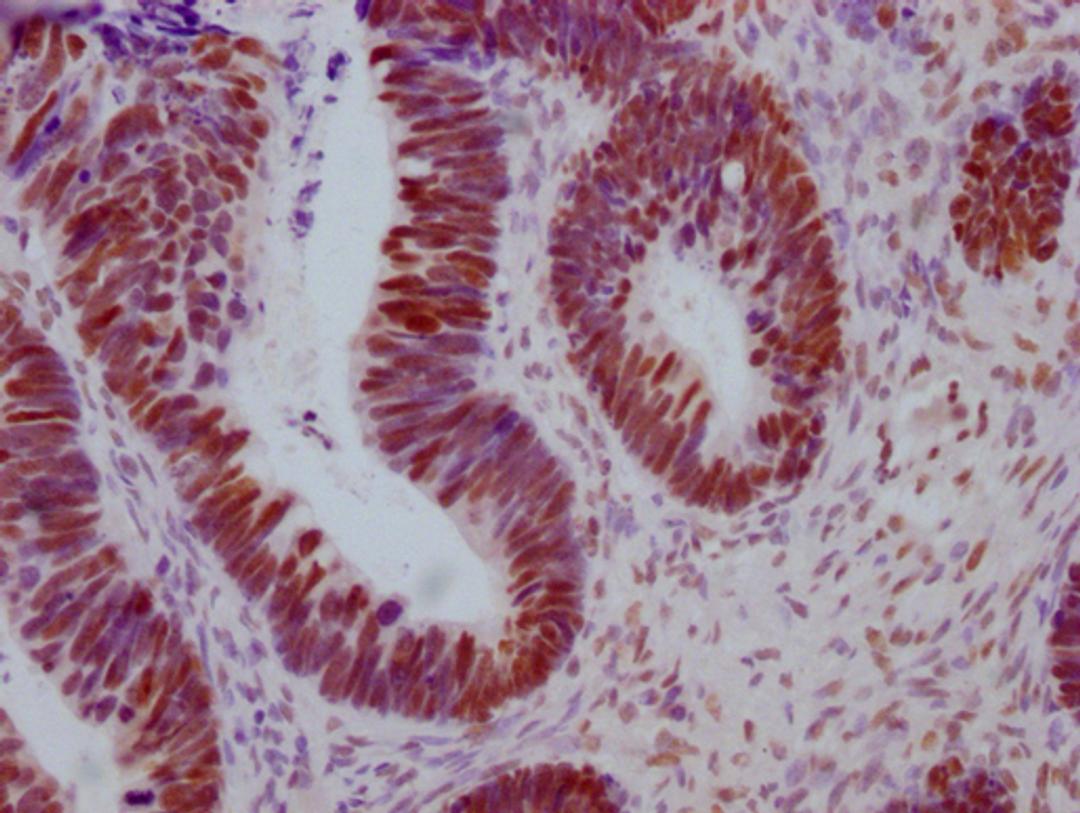

IHC image of CSB-MA442659 diluted at 1:100 and staining in paraffin-embedded human ovarian cancer performed on a Leica BondTM system. After dewaxing and hydration, antigen retrieval was mediated by high pressure in a citrate buffer (pH 6.0). Section was blocked with 10% normal goat serum 30min at RT. Then primary antibody (1% BSA) was incubated at 4°C overnight. The primary is detected by a Goat anti-mouse IgG polymer labeled by HRP and visualized using 0.05% DAB.